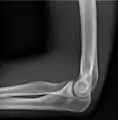

- آرنج - AP و جانبی. تصاویر موجود سر استخوان رادیوس در صورت درخواست.

پروجکشن جانبی

پروجکشن قدامی خلفی

پروجکشن مایل داخلی ۳۰ درجه آرنج چپ

پروجکشن مایل خارجی ۳۰ درجه آرنج چپ